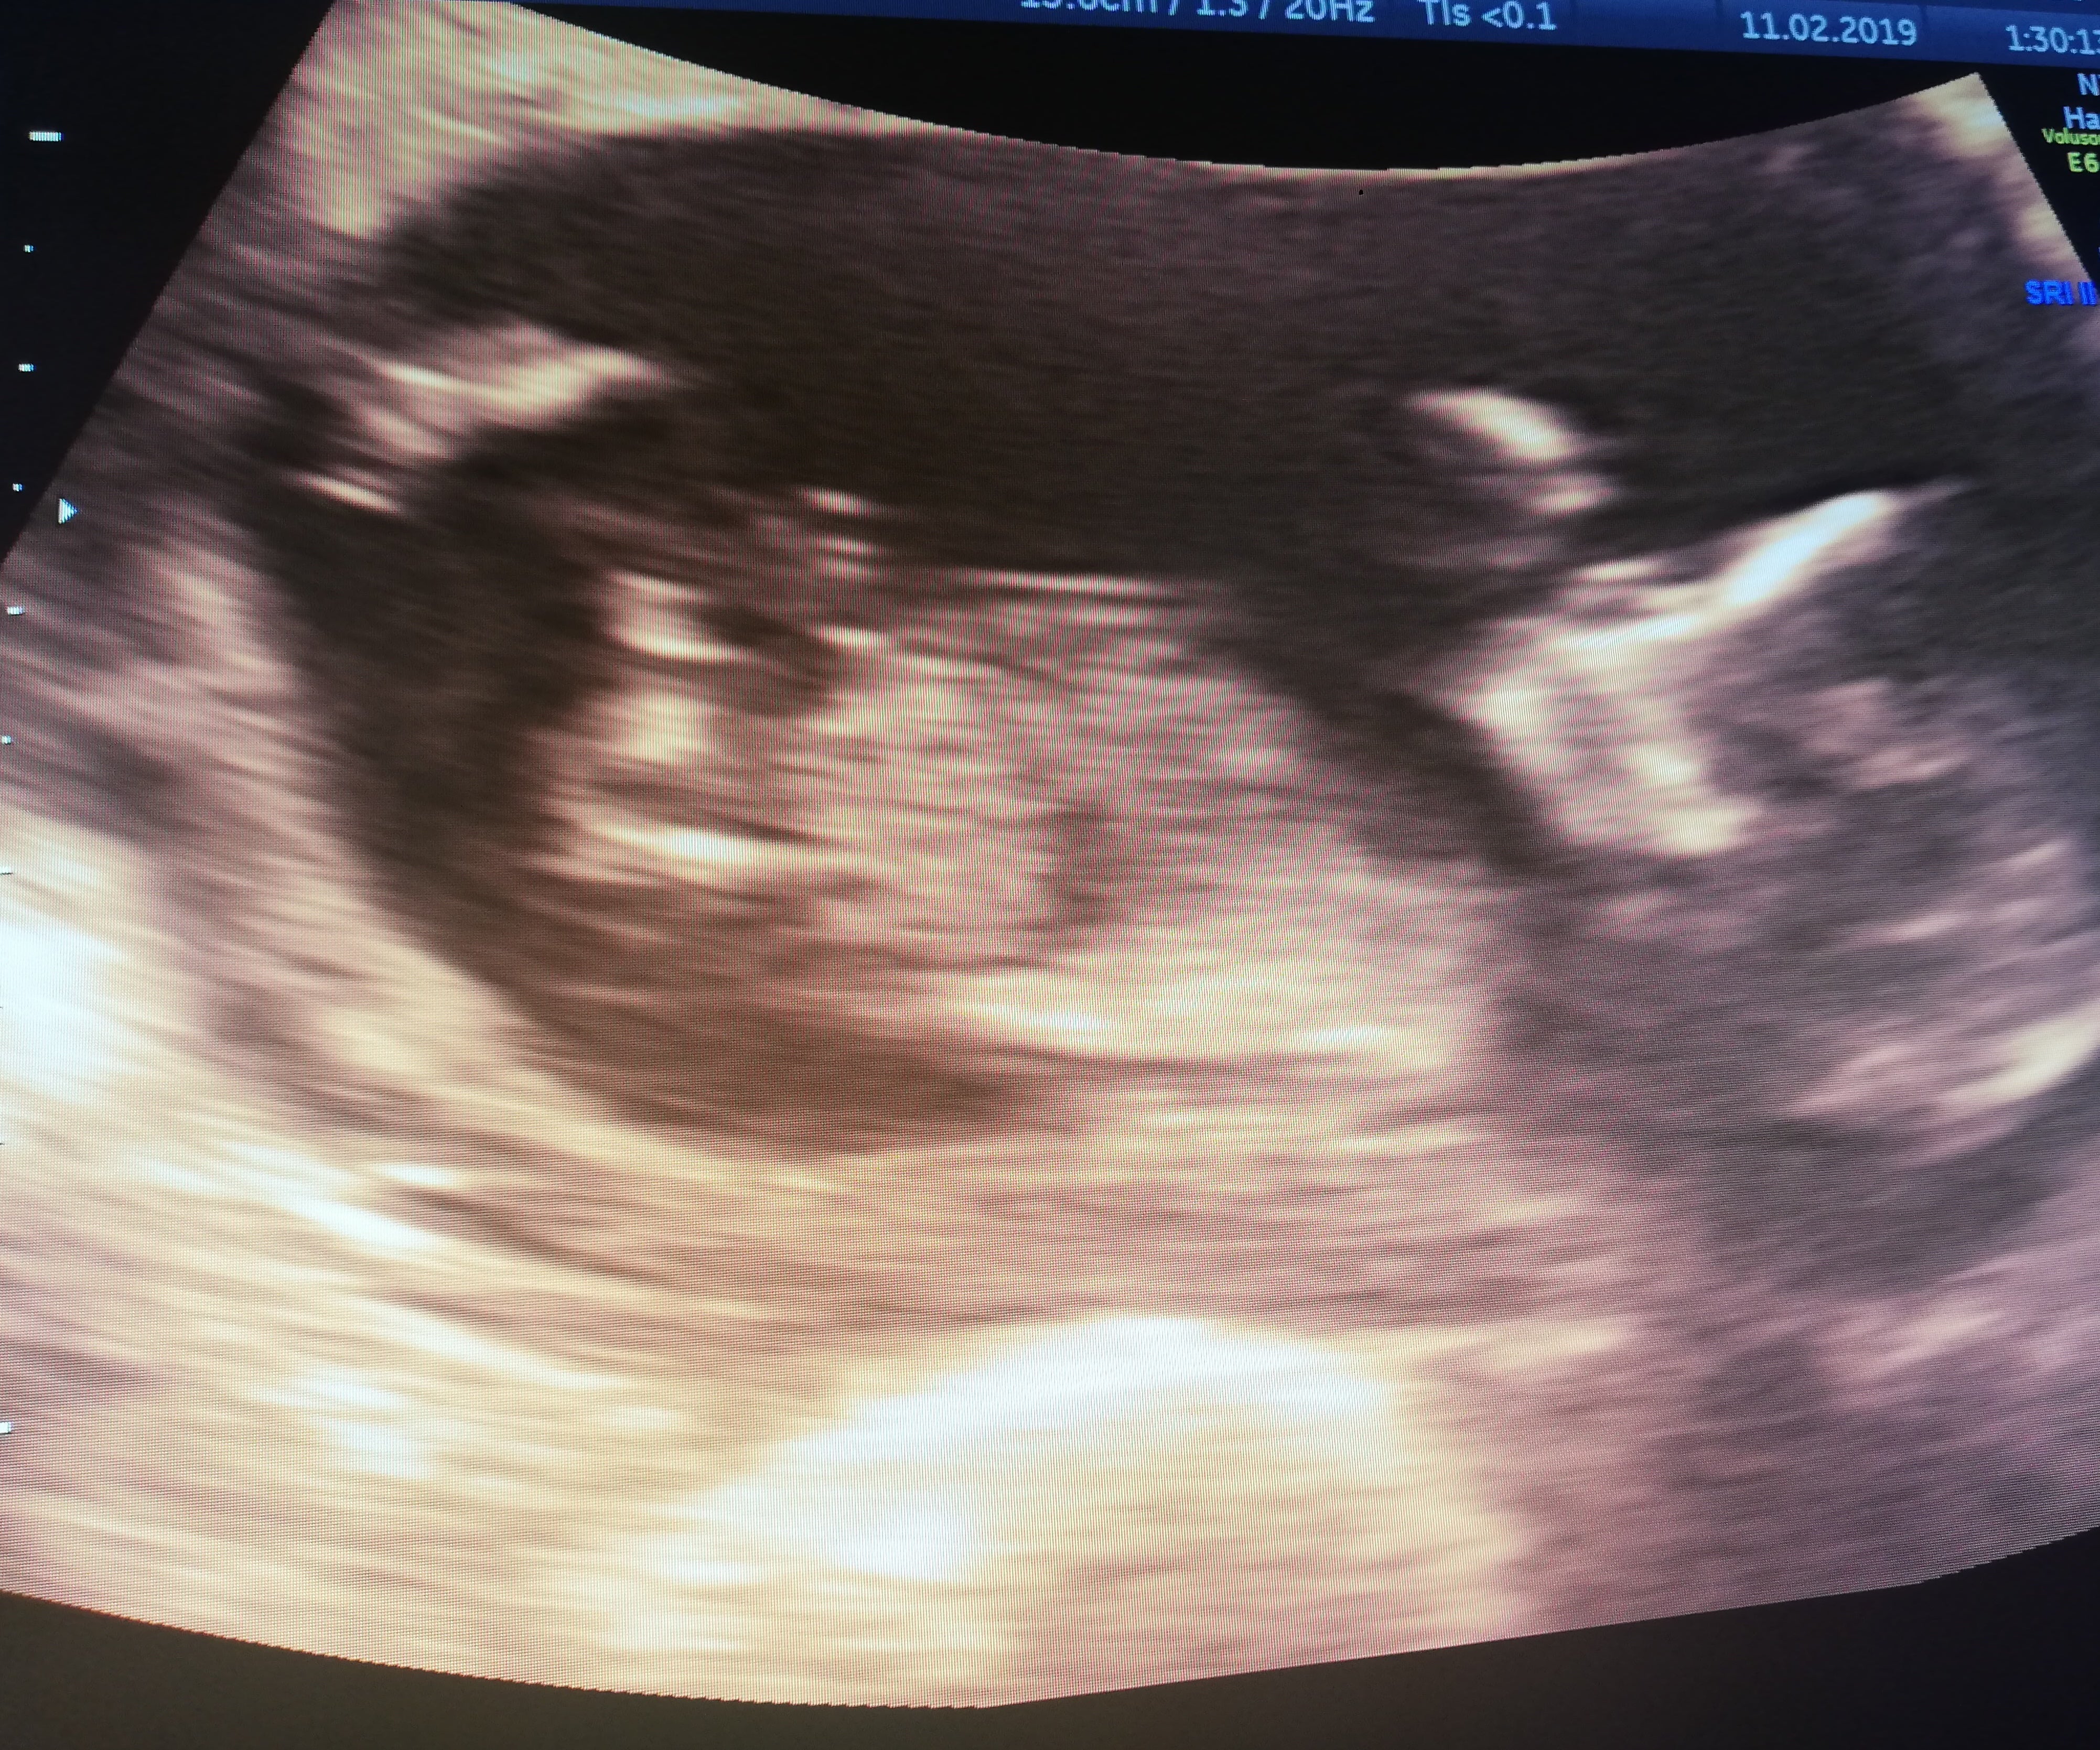

My husband and I would like to thank you from the bottom of our hearts for helping our dream of becoming parents come true. We have had our first scan and we are so pleased to introduce a little boy in August 2019!